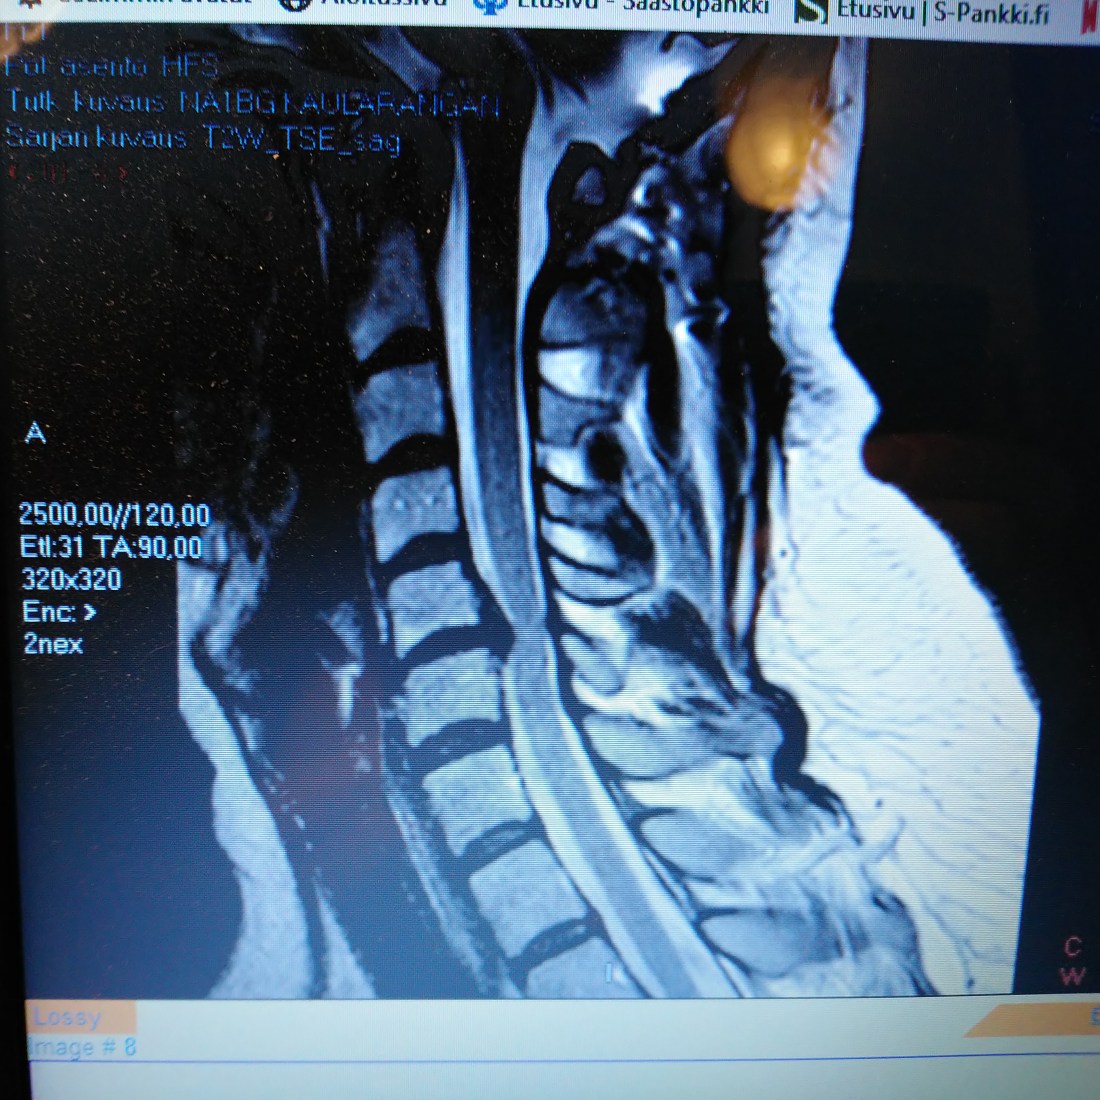

2017 joulukuussa leikattiin oikea ranne hermopinteen vuoksi ja vuoden lopussa tehtyjen magneettikuvien saldona löytyi kaularangasta C 5-6 väliltä viallinen nikama, joka painaa selkäydintä vaikeuttaen selkäydin nesteen kulkua. Jalkojen ja käsien lihasheikkoudet johtunee pitkälti selkäytimen ongelmasta.

Nyt 2018 huhtikuussa olin jälleen siis leikkuupöydällä. Neurokirurgin kanssa keskustelin kaularangan leikkauksesta ennen sairaalaan menoa. Jälleen selitettiin leikkauksen kulkua ja riskejä. Riskit aika itsestäänselvät, ollaanhan selkäytimen ympärillä työskentelemässä. Ainoa asia mikä jäikin kunnolla mieleen oli sanat – Vahinkoja valitettavasti sattuu. Jos selkäydin jostain syystä vahingoittuu eivät jalat toimi enää koskaan ja kädetkin hyvin heikosti.

Operaatiossa viallinen nikama C 5-6 väliltä poistettiin ja tilalle laitettiin proteesi luumassakiinnityksellä.